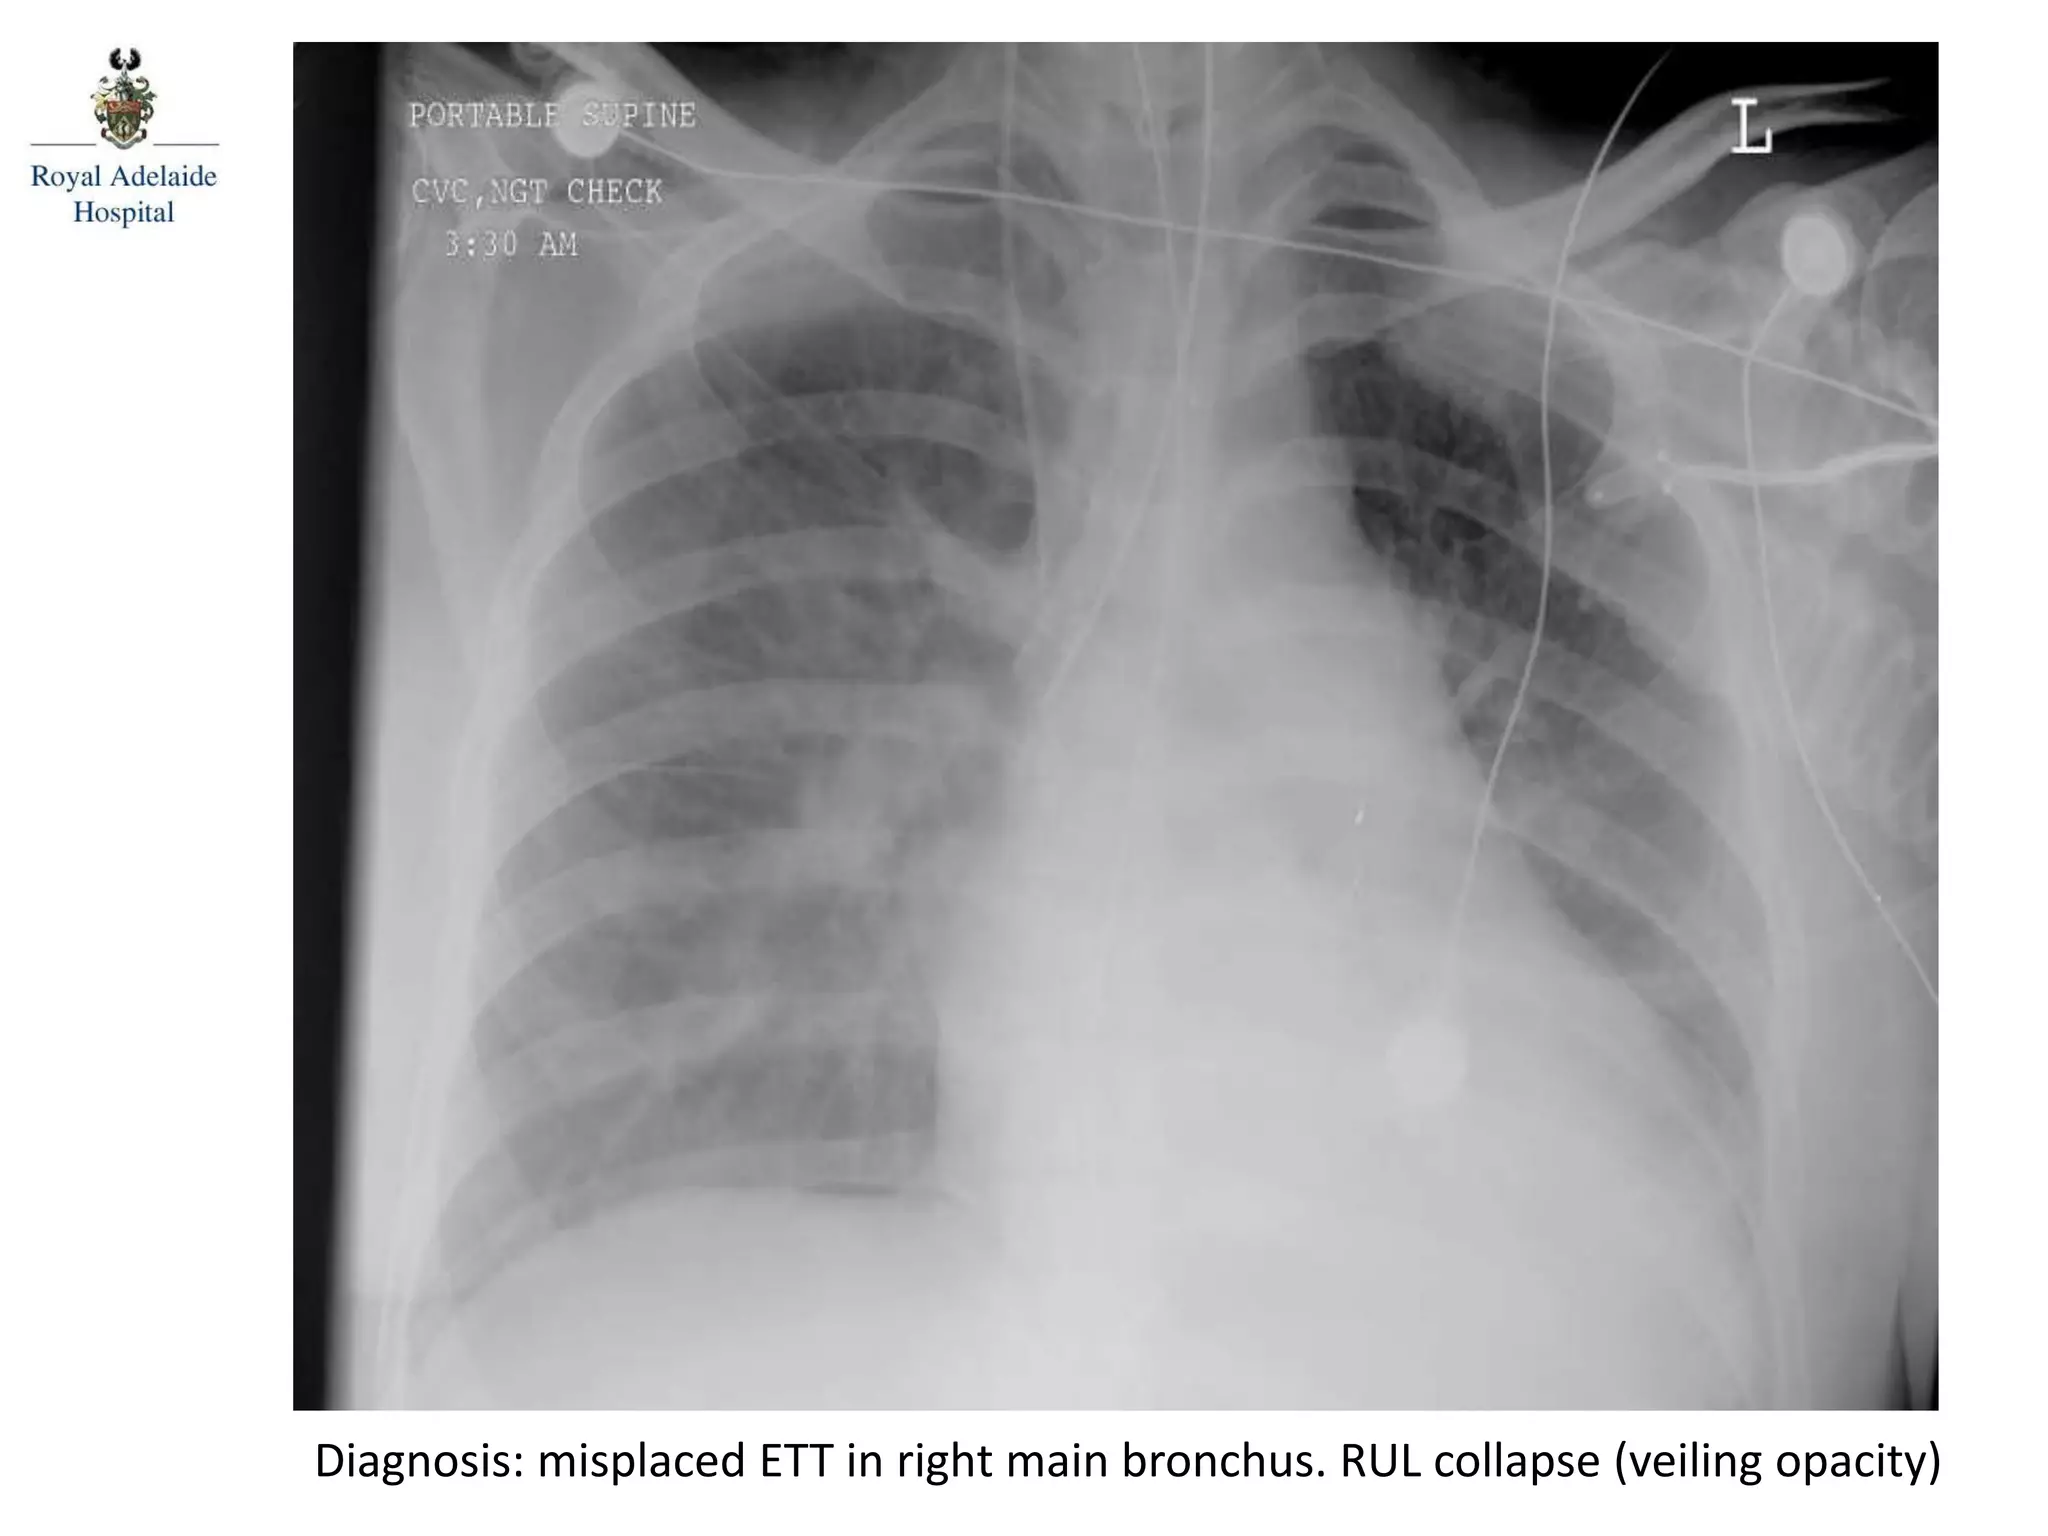

Diagnosis: misplaced ETT in right main bronchus. RUL collapse (veiling opacity)